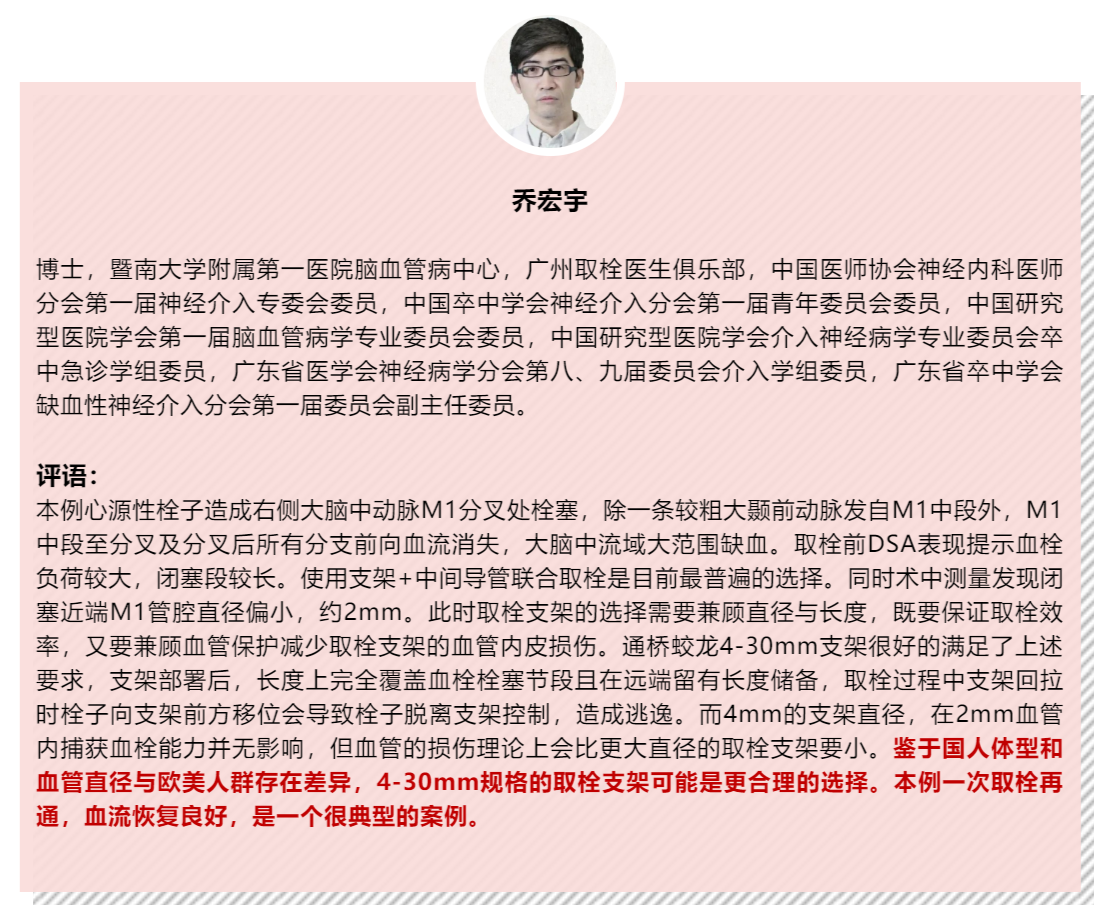

该病例是心源性栓塞,血栓质韧,本例选用蛟龙4*30mm更长的取栓支架,更长长度提供更大表面积接触血栓,以独特的侧边螺旋开放结构,帮助快速高效一次三级再通。一篇研究回顾性分析了2011年6月到2017年3月使用直径4mm取栓支架及球囊指引导管作为首选治疗策略治疗ICA、MCA急性闭塞的病例。该研究中,4×30mm和 4×40mm被定义为长支架,4×20mm被定义为短支架。主要的临床结局是一次性取栓血管成功再通率(mTICI 2b/3)。研究共纳入420例患者,其中221例(53%)患者使用长支架,119例(47%)使用短支架。相对于短支架,长支架组一次性取栓血管开通率(62% vs 50%;P=0.01)和最终血管开通率(mTICI2b/3,98% vs 94%;P=0.01)更高。长支架一次性取栓成功开通率高的原因,可以从以下几方面来解释:长血栓会提供更大的表面积与取栓支架接触包裹血栓,也会在取栓过程中使张力均匀分布,在血管路径扭曲或者躁动的病人中,长支架通过增加可接受的误差范围来实现精确释放。更长的支架会增加取栓装置向血栓远端延伸的移动力,同时,在支架首个与血栓接触的网孔抓捕血栓失败的情况下,可以增加血栓取出的机会。[1]因此,通桥医疗即将上市的蛟龙4*30mm取栓支架在临床上的广泛应用值得期待。

专家点评